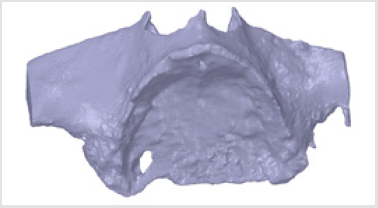

Subperiosteal implant design started with the processing of CBCT images. Figure 1 shows STL files of the patient’s mandibula, which is the lower jawbone. Figure 2 shows STL file of the patient’s maxilla, which is the upper jawbone. Figure 3 shows the result of virtual planning with the maxilla, mandibula, the designed implant, and denture. The final subperiosteal implant was designed based on CBCT images. Mechanical aspects were also considered in the design process of the titanium framework. Figure 4 shows the STL file of our titanium implant design with its three-dimensional geometry that had been analysed with finite element method.